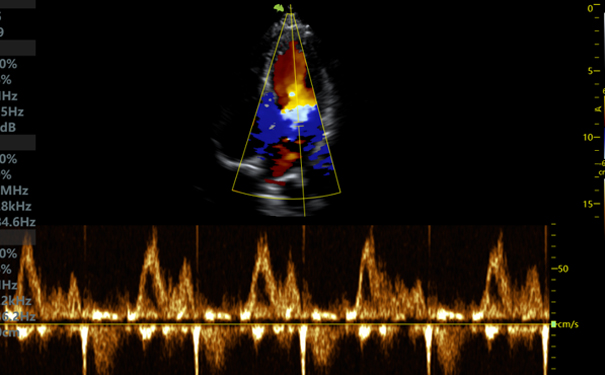

心脏监测

推荐型号:VINNO Q-2P

由于心脏检查比较复杂,成像要求更高,一直是掌上超声产品的研发难点。VINNO Q-2P具备优异的心脏二维图像表现力,对各心腔和血管的大小、厚度及完整性,各瓣膜结构与功显示清晰。同时,还拥有左室心内膜自动描记Auto EF、 M 型/全方位 M 型等专业心脏模式。能在围术期协助医生对危重病人做出快速检查评估和监测。

掌上超声心脏图像